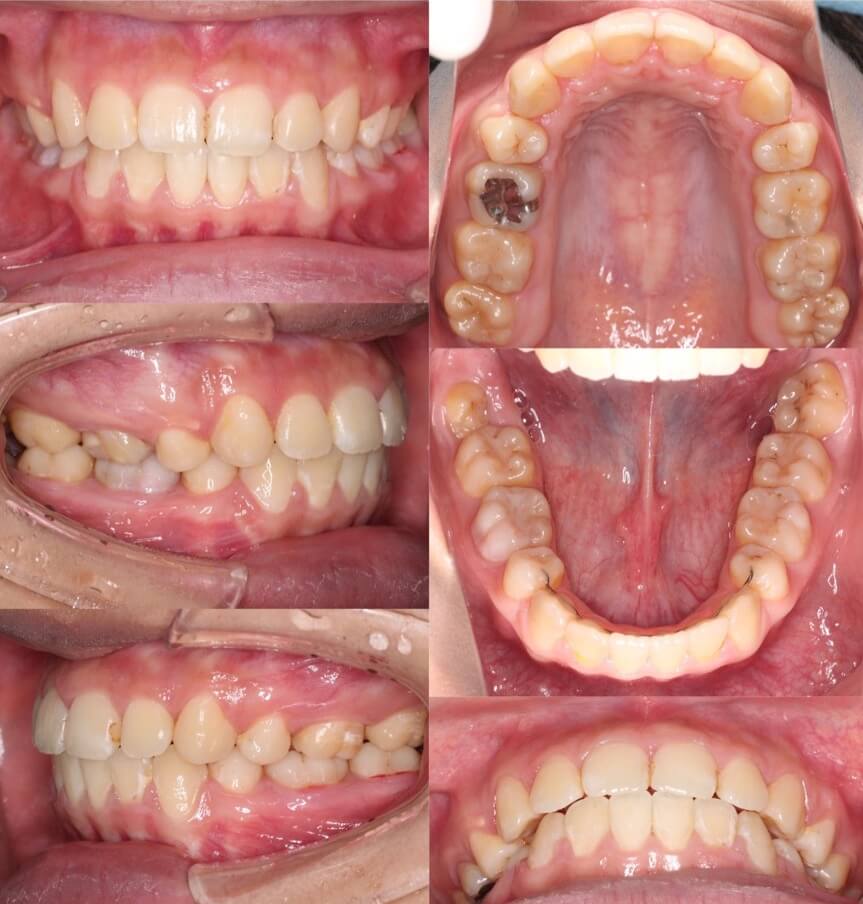

「マウスピースの後方移動の限界」

20代女性・マウスピース型装置・下あご後退型

奥歯の固定が弱いマウスピース型矯正装置の場合は、ワイヤー型矯正と比較して若干、前歯の引っ込む量が少なくなります。ですが、患者さんの希望する治療のゴールによっては、このように問題なく改善は見込めます。

<症例概要> 難易度:★★★★★

主訴:横顔で口が前に出ている

年齢・性別:20代女性

住まい:千葉県佐倉市

症状:下顎後退・上下顎前歯唇側傾斜

治療方針:抜歯空隙の閉鎖(中等度固定)

治療装置:マウスピース型矯正装置(アライナー装置)

抜歯:上下顎第一小臼歯

治療期間:2年2か月

アライナー枚数:55+33+21ステージ

リテーナー:上下クリアタイプ+フィックスタイプ

治療費用:990,000(税込)

代表的副作用:痛み・治療後の後戻り・歯根吸収・歯髄壊死・歯肉退縮

【治療シミュレーション】

上下の抜歯スペースに犬歯から順番に移動させる治療計画です。奥歯のかみ合わせが悪くならないようゴムをかけてもらうようにしています。